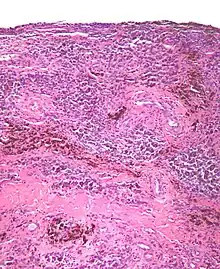

| Micrograph of diffuse TGCT, also known as pigmented villonodular synovitis. H&E stain. | |

Tenosynovial giant cell tumor (TGCT) is a non-malignant tumor defined histologically as inclusions of “osteoclast-like” multinucleated giant cells, hemosiderin, and macrophages.[1] This histology can present one of 2 clinically distinct ways. TGCT tumors often develop from the lining of joints (also known as synovial tissue).[2][3][3]: 100 [4][4]: 245 . Localized/nodular TGCT (L-TGCT), sometimes referred to as “giant cell tumor of the tendon sheath”;[3]: 100 is a common tumor that presents as a slow-growing, encapsulated, localized and limited bump, most frequently in the fingers. [5] Diffuse TGCT (D-TGCT) — also called pigmented villonodular synovitis (PVNS)— is a rare tumor that presents as a proliferative, destructive, intra-articular lesion, most commonly in the knee.[3]: 102 [6] Common symptoms of TGCT include swelling, pain, stiffness and reduced mobility in the affected joint or limb.[3]: 102